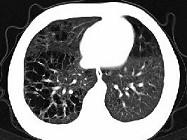

问题 男,3岁,活动气喘,查体压头颅骨有乒乓球感,肝脾大,根据影像学检查图像,最可能的诊断为 ( )

选项 A.肺间质纤维化 B.组织细胞增生症 C.先天性支气管扩张 D.先天性肺囊肿 E.肺发育不良

答案 B